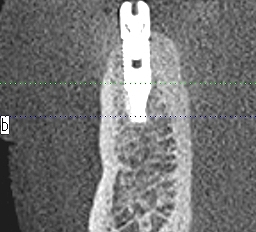

埋入後CTになります

6番あたりになります